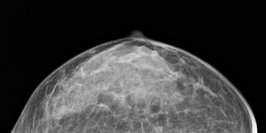

Die Mammographie ist der wichtigste bildgebende Beitrag zur Erkennung von bösartigen Brusttumoren (Mammakarzinom). Wir führen die Mammographie in dosissparender digitaler Technik auf einem Gerät der neuesten Generation durch. Zusammen mit dem Brustzentrum des Klinikums Lüdenscheid fertigen wir Mammographien zur Erkennung von Brusttumoren und zur Behandlungsplanung an.

Darüber hinaus werden in unserer Klinik in enger Kooperation mit der Frauenklinik verdächtige Brustbezirke mit speziellen Nadeln markiert. Anhand dieser Markierungen können die Operateure dann gezielt Gewebe entfernen, das anschließend feingeweblich (histopathologisch) im Institut für Pathologie untersucht wird. Im Rahmen der Qualitätssicherung werden in einer wöchentlichen Konferenz die radiologischen, histopathologischen und klinischen Ergebnisse miteinander besprochen. Hierbei nehmen regelmäßig auch niedergelassenen Kollegen teil.

Eine neue Technik stellt die stereotaktische Vakkumbiopsie nicht tastbarer Läsionen dar. Hierbei können unter radiologischer Kontrolle Herde aus der Brust entfernt und feingeweblich untersucht werden.

Selbstverständlich werden bei uns auch Spezialverfahren wie die Milchgangdarstellung (Galaktographie) und der Ultraschall der Brustdrüse angeboten und durchgeführt.